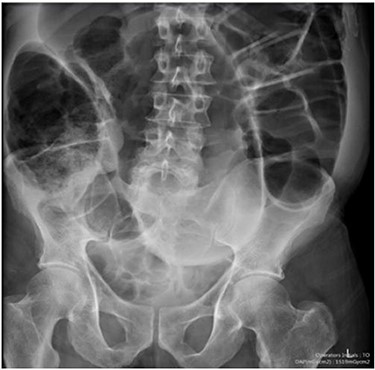

Blood tests on admission were unremarkable, with normal electrolytes levels and lactate. A plain abdominal film showed a typical appearance of caecal volvulus, with an inverted ‘comma sign’ (Fig. 4). A CT scan of the abdomen and pelvis with intravenous contrast was reported as sigmoid volvulus with the involved loops sitting predominantly in the right upper quadrant immediately inferior to the liver (Fig. 5).

Case two: a coronal slice of a CT scan of the abdomen and pelvis with intravenous contrast showing dilated large bowel loops; the radiology report suggested sigmoid volvulus with a centrally lying caecum.